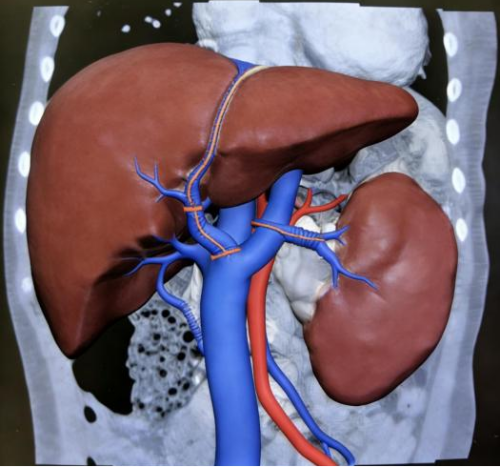

历时10小时17分钟的连续奋战,手术成功最终取得圆满成功。术中超声显示,桥血管血流通畅,出血仅150ml。术后CTA检查证实,重建血管通畅,门静脉高压根本缓解,患儿消化道再出血的风险彻底解除。

术后血管重建影像:肝门搭桥血管血流通畅、脾脏较术前缩小